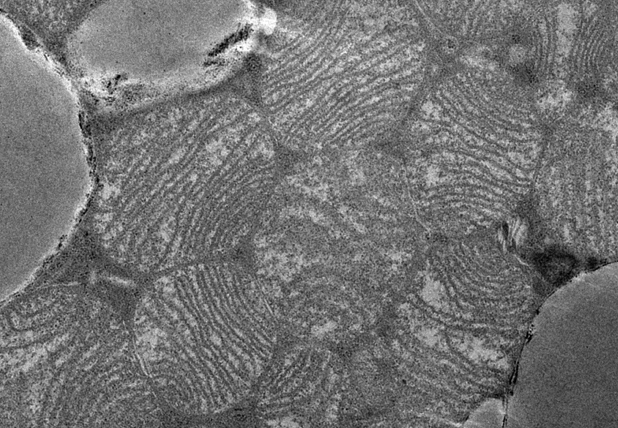

Bei Menschen und Säugetiere unterscheidet man generell zwischen zumindest zwei verschiedenen Fettdepottypen, dem weißen und dem braunen Fettgewebe. Ersteres kommt im menschlichen Körper viel häufiger vor, speichert Fett, und befindet sich vorzugsweise in den allgemein bekannten Polstern an Bauch, Gesäß und Oberschenkeln. Bei erhöhtem Energiebedarf kann der Körper auf diese Depots zurückgreifen. Braunes Fett hingegen verbrennt Energie unter Freisetzung von Wärme, weswegen Babys auch folglich viel davon haben. Nach dem Neugeborenenalter sowie bei Übergewicht nimmt die Anzahl dieser Zellen allerdings stetig ab.

„Das braune Fettgewebe wurde als Möglichkeit identifiziert beim Abnehmen zu helfen, weil es große Mengen an Kalorien verbrennen kann“ erklärt Elena Schmidt, die als Doktorandin in der Forschungsgruppe von Jan-Wilhelm Kornfeld in Köln arbeitet. Alleine 40-50 g braune Fettzellen könnten 20% mehr Kalorien verbrennen. Deshalb stelle eine Aktivierung der braunen Fettzellen eine neuartige Möglichkeit dar um abzunehmen.